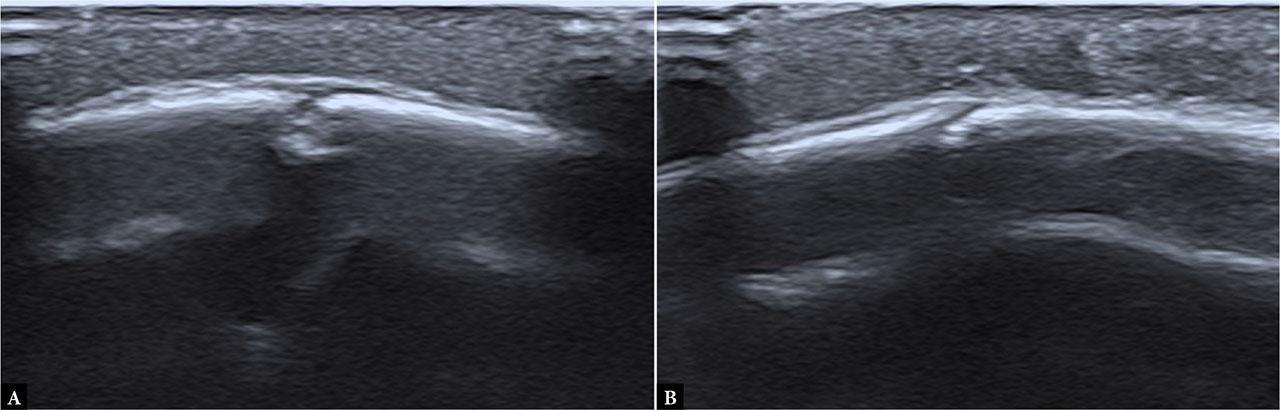

All patients were first clinically evaluated by a pediatric surgery resident or specialist in the emergency department. Based on surgical assessment, patients were referred to the radiology department, where ultrasound examinations were performed in a dedicated ultrasound room using a CANON Aplio i700 ultrasound machine, equipped with a high-frequency linear transducer (11–18 MHz). Children were positioned supine or, in cases of occipital trauma, in a prone or sitting position, accompanied by a caregiver, with gentle immobilization applied when necessary to minimize motion artifacts. The area of impact, hematoma, or maximal tenderness was systematically scanned in both longitudinal and transverse planes, with additional sweeps of adjacent and contralateral regions for comparison. In the absence of clear clinical signs of impact area, or problems with indicating the expected site of injury (non-verbal children), a broader portion of the skull was routinely examined. Particular attention was paid to differentiating fracture lines from normal cranial sutures at the affected site by tracing sutures to a fontanelle where possible or by comparing with symmetric contralateral structures. Major cranial sutures were assessed only at the affected site and adjacent collateral locations to distinguish normal suture lines from potential diastasis. ( Fig. 1, Fig. 2, Fig. 3, Fig. 4) No cases of sutural diastasis were identified in the cohort. All scans were performed by 15 radiology department physicians, either trained pediatric radiology residents or board-certified specialists. Interobserver variability was not formally evaluated.

Normal cranial sutures in (A) a 4-month-old and (B) a 6-month-old boy, which may mimic a fracture line. The overlying soft tissues show normal echostructure above the suture line